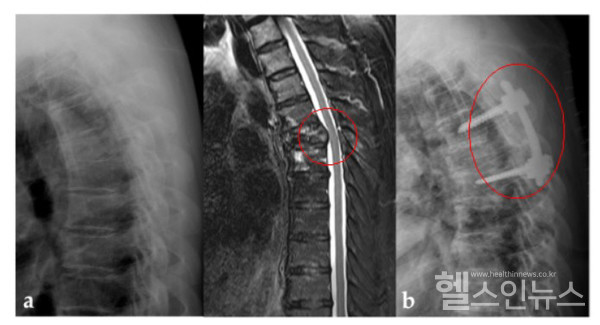

가톨릭대학교 서울성모병원 정형외과 김영훈 교수(교신저자)·은평성모병원 정형외과 박형열(제1저자) 교수팀은 ‘비소세포폐암 척추 전이 환자의 척추 수술과 방사선 치료 병합 요법 중요성’을 연구한 논문을 국제학술지에 게재했다. 2011년부터 2017년까지 비소세포폐암의 척추 전이로 척추 수술과 방사선 치료 병합 요법을 시행한 22명을 선정하였다. 이 후 환자를 나이, 성별, 기대 수명, 척추 불안정성을 고려한 1:1로 경향 점수 대응을 통해 방사선 단독 치료만 진행한 시행한 231명 중 비슷한 조건의 22명과 비교하였다.

그 결과 방사선 단독 치료 군에서만 5명의 환자(22.7%)가 병적 골절로 인한 신경학적 증상의 악화가 관찰되었다. 또한 수술과 방사선 치료를 시행한 군에서는 보행이 불가능했던 4명의 환자가 보행이 가능하게 되었으며, 5명의 환자는 신경학적 증상이 개선되었다.

김영훈 교수는 “비소세포폐암이 척추로 전이된 환자는 임상적으로 흔하지만 치료방법을 결정하기 쉽지가 않은데, 수술적 치료가 병적 골절 예방을 통해 장기적으로 신경학적 증상의 악화를 막을 뿐만 아니라, 신경학적 결손이 발생한 환자에서 직접적인 신경 감압을 통해 보행과 신경학적 증상을 호전시키는 효과를 보인다는 것을 이번연구로 확인하였다”고 설명하였다.